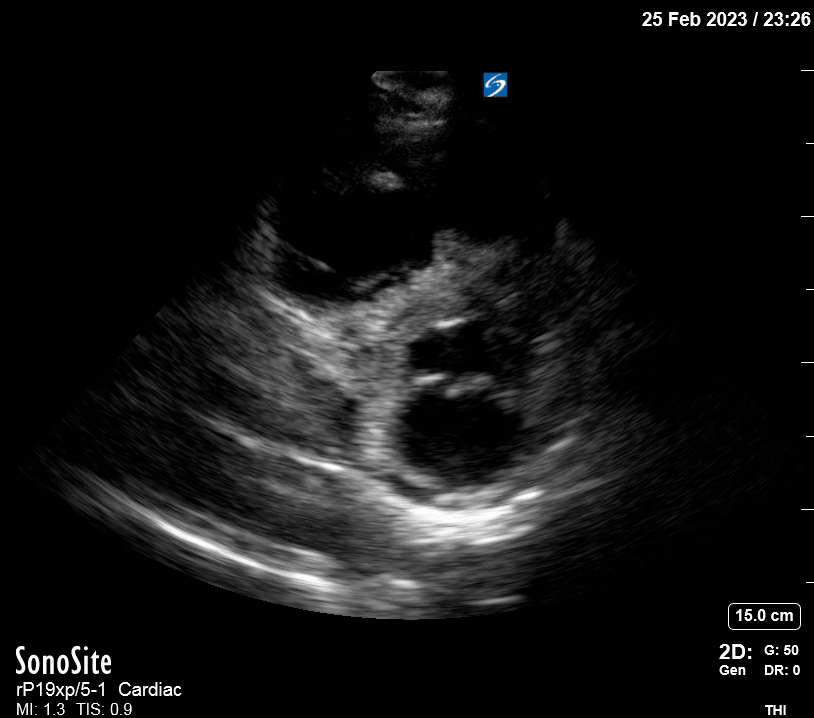

The A4C view provides an accurate chamber size comparison. However, achieving a proper A4C view (avoiding foreshortening or ballooning, and visualising the four chambers with a vertically oriented interventricular septum) can be a challenging exercise of image acquisition. Additionally, the PSAX view at the level of the papillary muscles shows both LV and RV side by side and is useful to assess function and size. When RV pressure is high, the septum will be pushed and flattened towards the LV, resulting in the characteristic “D-shaped” LV or “D sign”.

PITFALLS

When comparing size, beware of correct image acquisition, as oblique planes lead to misinterpreting the RV:LV ratio. For apical views be sure to slide the probe sufficiently laterally on the chest wall so that it lies over the true apex. Also, be sure to obtain a real horizontal plane, avoiding foreshortening (ballooning). For the PLAX view it is useful to fan through the heart’s long axis, making sure that LV visualization is maximized relative to the RV. Furthermore, an understanding of probe placement and marker orientation conventions is fundamental. If inadvertently scanning in reverse orientation, the normally larger LV could be mistaken for an abnormally enlarged RV.